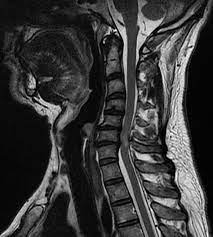

Cervical Disc Prolapse

Disc bulge in the neck pressing nerves, causing neck pain, arm pain, tingling, numbness, and sometimes weakness in hands or arms.

Cervical / Dorsal Myelopathy

Compression of the spinal cord in neck or upper back causing imbalance, clumsy hands, weakness, stiffness, and difficulty in walking.

OPLL

Abnormal ligament bone formation inside the spinal canal compresses the spinal cord, leading to neck pain and stiffness.